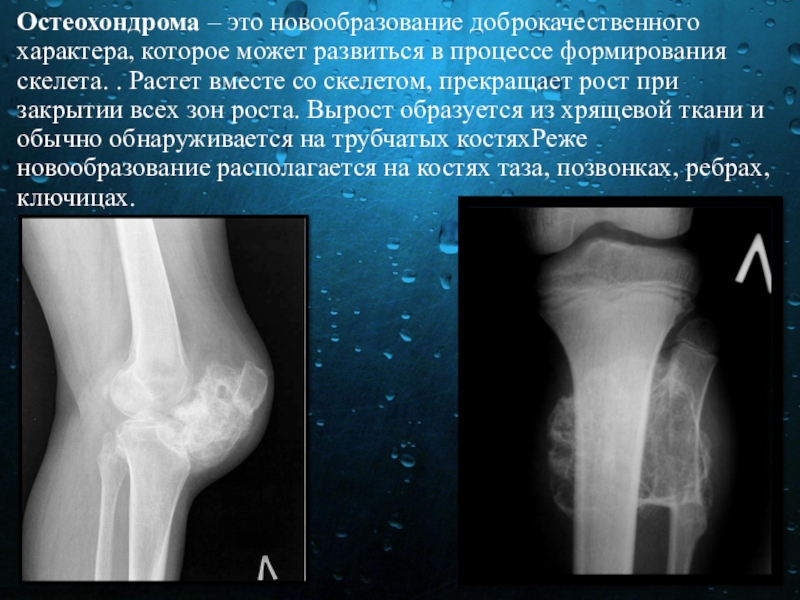

Слайд 15Остеохондрома – это новообразование доброкачественного характера, которое может развиться в процессе формирования скелета. .

Растет вместе со скелетом, прекращает рост при закрытии всех зон роста. Вырост образуется из хрящевой ткани и обычно обнаруживается на трубчатых костяхРеже новообразование располагается на костях таза, позвонках, ребрах, ключицах.